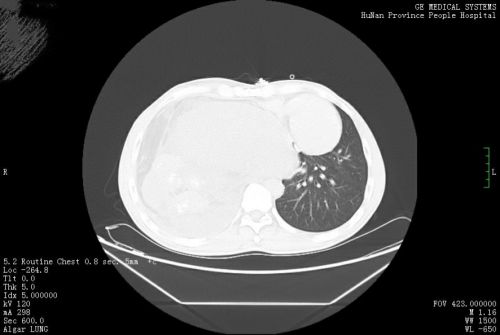

术前ct显示:包块挤压右肺。

术后ct显示:右肺清晰可见。

胸部CT检查发现,其右侧胸、腹腔内有一个巨大包块压迫右肺,因此出现胸痛、胸闷等不适。进一步检查考虑,巨大包块来源于后纵膈,畸胎瘤的可能性大。心胸外科医师会诊后,将他收入心胸外科病房准备手术治疗。

开胸探查发现,徐先生右侧胸腔内的肿块质地坚硬,呈长椭圆形,像个“大冬瓜”,向上抵达胸腔顶部,向下推挤膈肌至脐水平,直径约40cm、横径约25cm。术中,主刀医师依次切除胸腔内肿块各分叶后,发现仍有少部分瘤体粘连在左心房底部,只得切除少许心房壁。